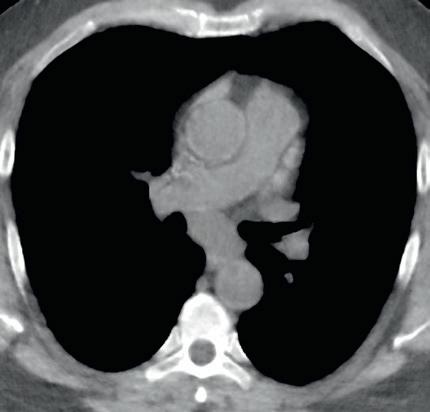

Most DECT datasets can be used to generate additional virtual monoenergetic images (typically between 40 and 60 keV [kilo electron volts]) that have high-contrast enhancement because they are close to the k-edge of the iodine. To minimize contrast streak artifacts and image noise in larger patients, higher keV images ( >70 keV) may be necessary. Iodine or pulmonary blood volume images represent material decomposition images (obtained from subtracting water from contrast-enhanced DECT images) that provide information on distribution of iodine in the lungs or remainder of the chest depending on the selected settings. The absolute iodine concentration expressed as milligrams per milliliter can be calculated from pulmonary blood volume images (Fig. 1.10). One can also generate water or virtual noncontrast images from contrast-enhanced

DECT by subtracting iodine from the image datasets to differentiate calcium, hemorrhage, or high-protein content from iodinated contrast (Fig. 1.11). The DECT technique also allows generation of higher keV images, which can help reduce artifacts with metallic implants or prostheses (Fig. 1.12).

FIGURE 1.11 Virtual noncontrast image. A soft tissue density mass is seen in the subcarinal region on the 140-kV image (A). On the virtual noncontrast (VNC) image (B), after iodine substraction, there is no change in the density of the subcarinal mass, and therefore there is no evidence for enhancement. This mass is consistent with a nonenhancing bronchogenic cyst.